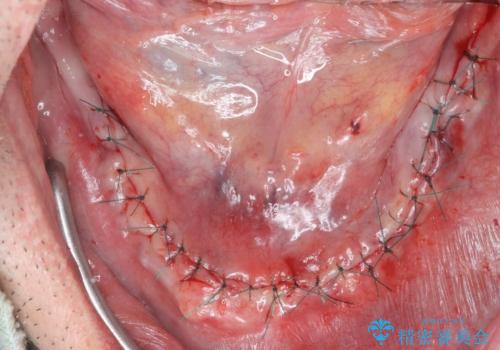

保存できる歯がなかったので全て抜歯をし、インプラントを埋入し、磁性アタッチメントを用いたインプラントオーバーデンチャーで治療を行いました。

- 外科手術のため、術後に出血、痛みや腫れ、違和感を伴います